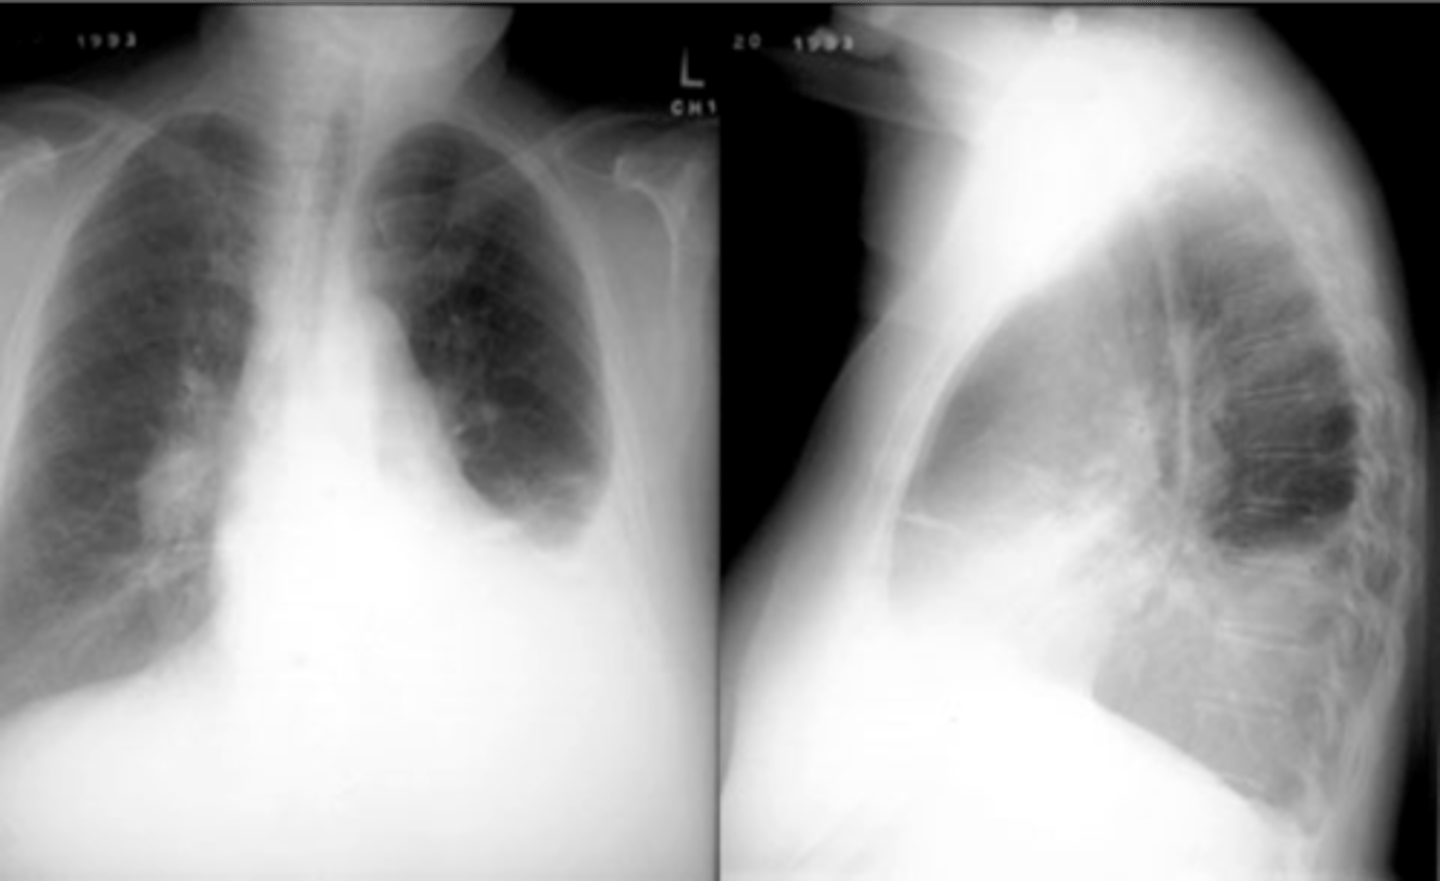

Bronchiectasis

knowt flashcard image

Tram track lines